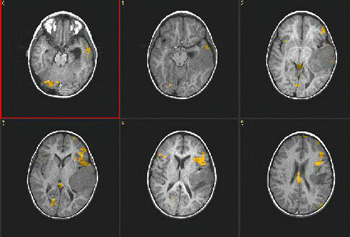

Case 4

| Patient | Male patient, 9 years old with a neoplastic lesion in the left sylvian fissure. No language deficit |

| Paradigm | Verbal fluency task ON: Think of actions related to given nouns OFF: Think of nothing |

| Results | Obvious left language dominance. |